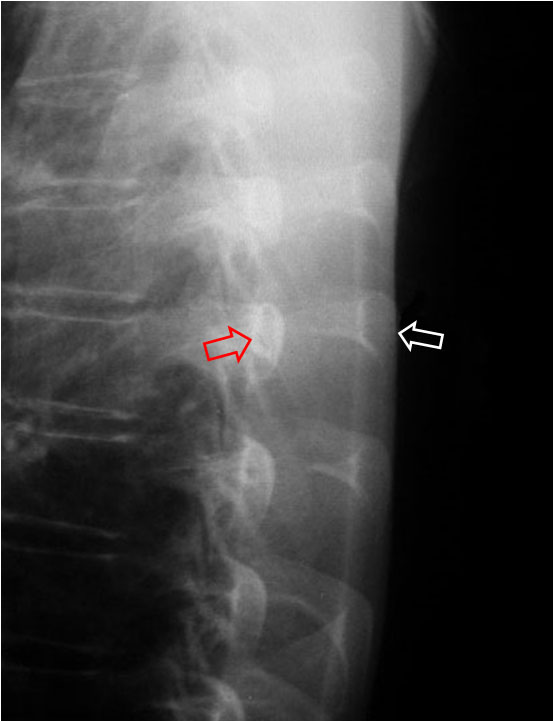

SIGNO DE LA COSTILLA GRANDE

En la radiografía lateral de tórax las costillas derechas –flecha blanca- se ven de mayor tamaño que las izquierdas –flecha roja-. Este hallazgo se identifica mejor si la radiografía está algo oblicua y no hay una superposición de las costillas, como vemos en la fotografía. La diferencia de tamaño está justificada por la mayor magnificación de las costillas derechas dado que, en la posición del paciente para la radiografía, el lado derecho está más alejado de la placa, según muestra el siguiente esquema.